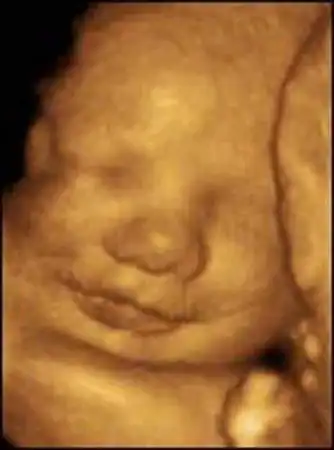

Уникальная ультразвуковая аппаратура, при помощи которой были получены эти видеозаписи, позволяет не только получать всевозможные фотографии плода, но и наблюдать за ним в реальном времени...

Создатель этой системы профессор Стюарт Кэмпбелл, один из ведущих акушеров Соединенного Королевства, стал знаменитостью в мире медицины благодаря снимкам, на которых зародыш улыбается (раньше считалось, что эта способность появляется лишь после рождения)...

Качество изображений превосходное!...

Специалисты признают, что эти снимки, прежде всего помогающие оценить правильность развития плода, завораживают...